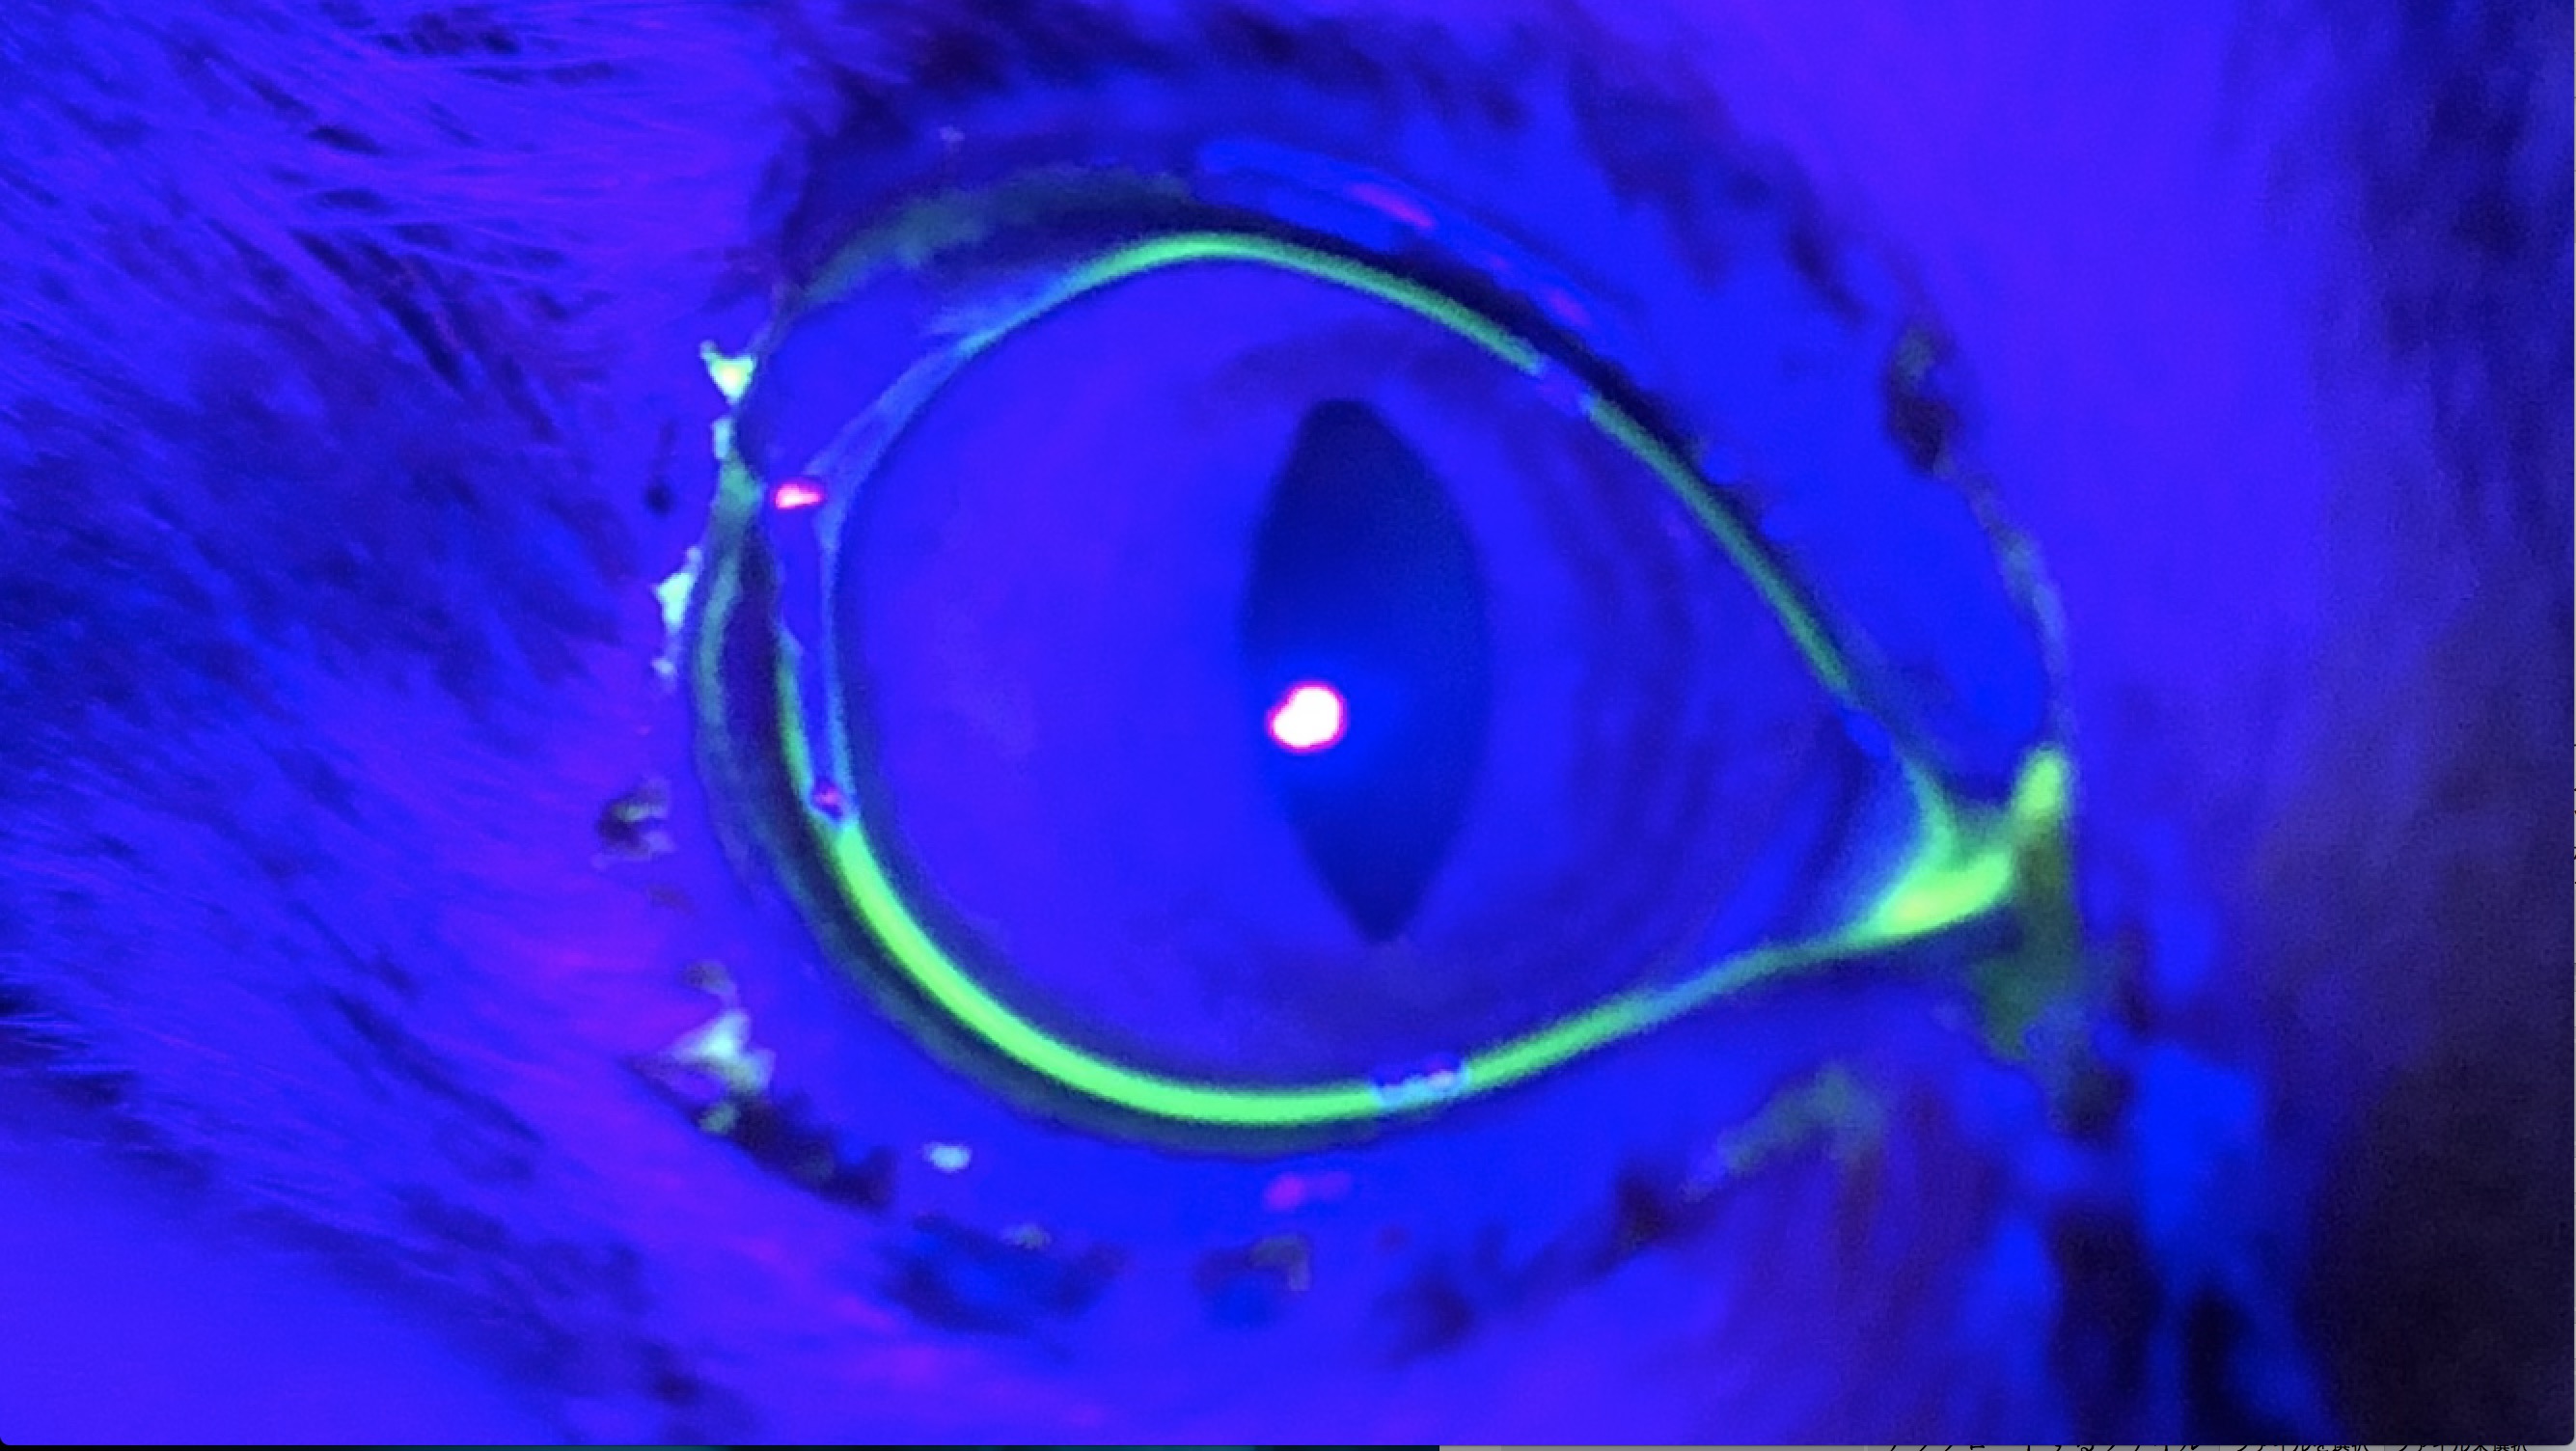

角膜潰瘍の猫の1例(目を気にする、目ヤニ、角膜)

目の染色検査を行ったところ中央部が黄色に染色されました。

染色部位は角膜が傷がついていることを示しています。

1週間後の染色検査です。

治療前にあった染色されていた部位は無くなり、本人も気にしなくなったとのことでした。

治療前

治療後